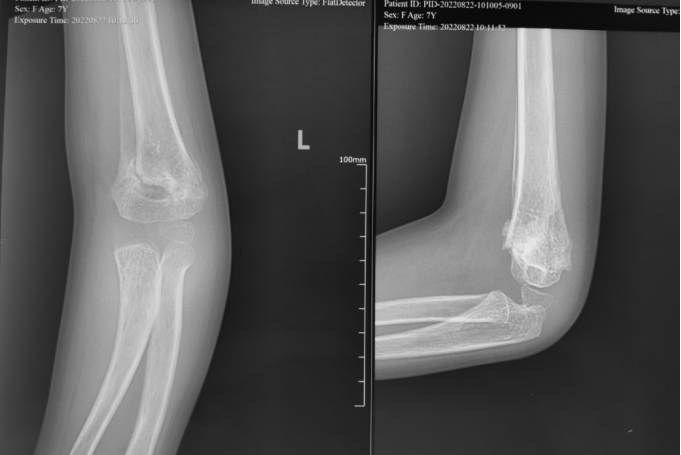

小玉(化名):女、9岁、3年前吊单杠时不慎摔伤致左肱骨髁上骨折,在当地医院行保守治疗。(下图为患儿X线片)

受伤当时X线片

手法复位后X线片

伤后一月后X线片

受伤后3年明显肘内翻畸形